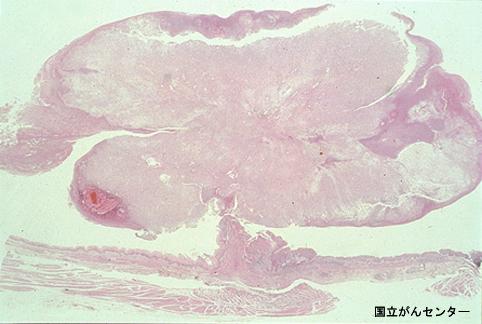

A case of type Ip+IIc carcinosarcoma of the esophagus with minute invasion to the submucosa.

Tokyo Pref., Cooperative study between National Cancer Center and Kyushu Cancer Center

Esophagus/Middle third

Type 0/I (I) Protruded type

40 -

Depth of Tumor Invasion

submucosa